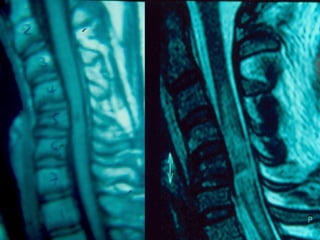

MMRRII

–UUsseeffuull ttoo eevvaalluuaattee

ddiissccrreeppaannccyy

bbeettwweeeenn cclliinniiccaall

eevvaalluuaattiioonn aanndd xx--

rraayy // CCTT ffiinnddiinnggss

–DDiisscc hheerrnniiaattiioonn

–LLiiggaammeennttoouuss

iinnjjuurryy

 MMRRII

– GGoooodd ffoorr vviissuuaalliizziinngg

ffrraaccttuurree aanndd mmuullttiilleevveell

ppaatthhoollooggyy

– PPrreeddiiccttss iinnssttaabbiilliittyy

bbeenneeffiittiinngg ffrroomm ffuussiioonn

pprroocceedduurree:: ddiissrruuppttiioonn ooff

aannyy 33 ooff tthhee aanntteerriioorr

lloonnggiittuuddiinnaall,, ppoosstteerriioorr

lloonnggiittuuddiinnaall,,

iinntteerrssppiinnoouuss aanndd ffaacceett

ccaappssuullee lliiggaammeennttss